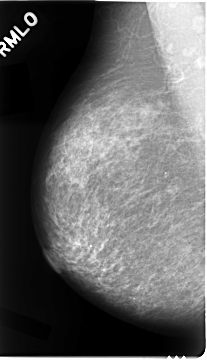

Digital Database for Screening Mammography

Volume: cancer_02 Case: C-0023-1

C_0023_1.RIGHT_MLO

RIGHT_CC LINES 4664 PIXELS_PER_LINE 2744 BITS_PER_PIXEL 12 RESOLUTION 50 NON_OVERLAY

RIGHT_MLO LINES 4680 PIXELS_PER_LINE 2680 BITS_PER_PIXEL 12 RESOLUTION 50 NON_OVERLAY